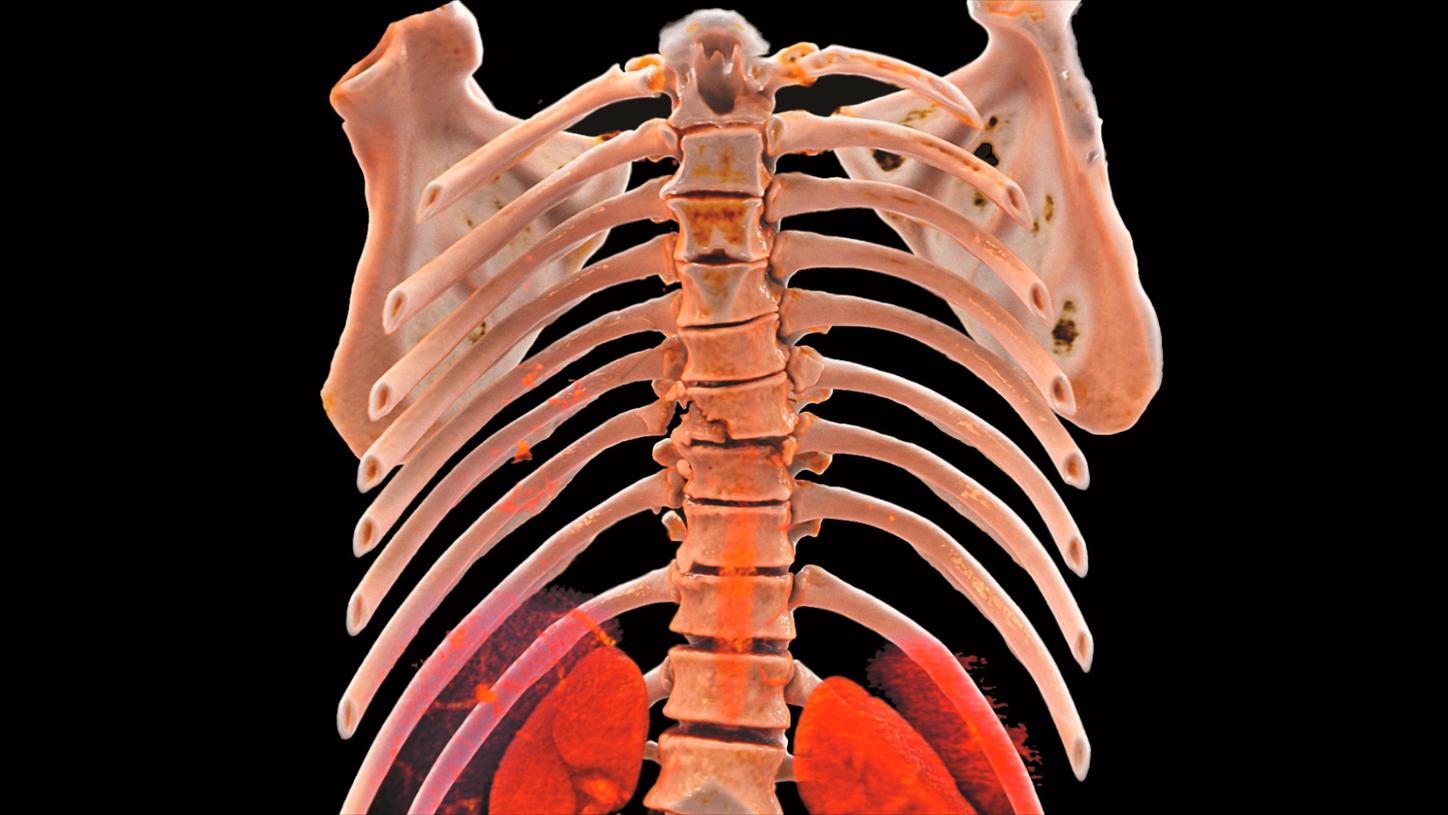

Computed Tomography is moving beyond its traditional diagnostic role to become a key player in early disease detection and therapy planning. This expansion means an even broader patient cohort and resilient productivity demands. You need a reliable partner with products, services, and the infrastructure to support new business models and prioritize environmental sustainability and robustness. Computed Tomography at Siemens Healthineers, with its legacy of listening for almost 50 years, is innovating ahead of these developments, even before potentials become needs.

The NAEOTOM Alpha class